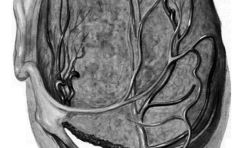

Im Bild

Trokarhernie PDF Dokument